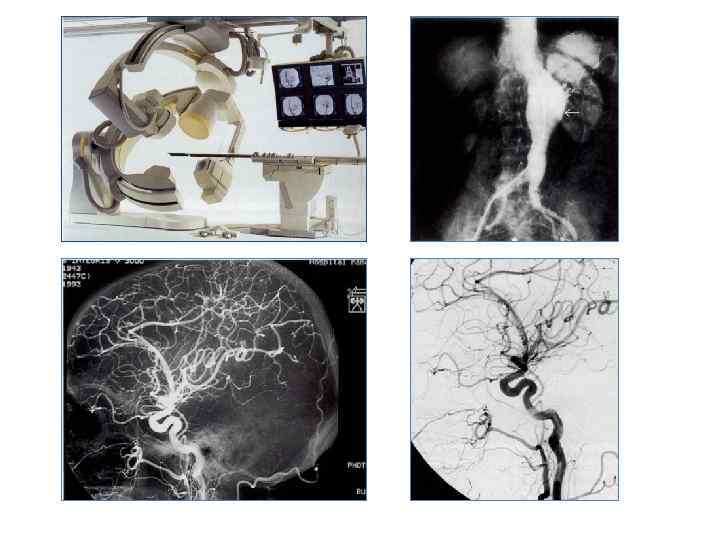

Ангиография абдоминального отдела аорты

Ангиография абдоминального отдела аорты

Ангиография артерий нижних конечностей

Ангиография артерий нижних конечностей

Эмболизация Аневризма передней соединительной артерии После эмболизации

Эмболизация Аневризма передней соединительной артерии После эмболизации